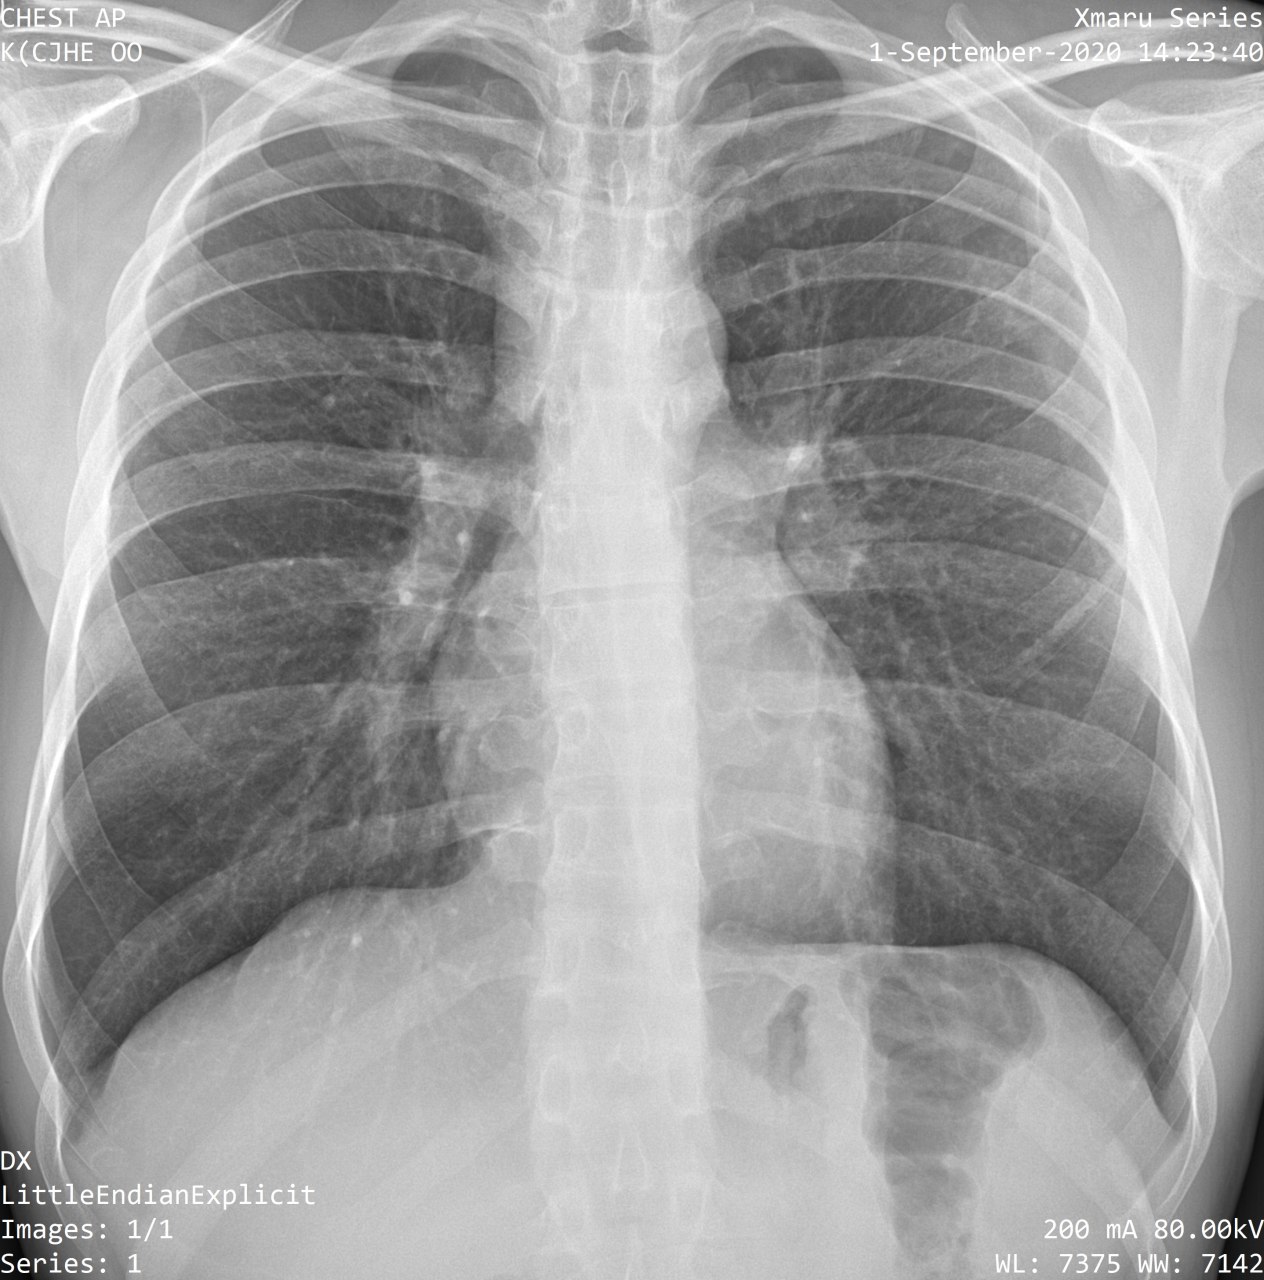

Подскажите пожалуйста, тут справа в нижних отделах, что-то есть или это сосуды?

С учётом рентген архива может быть  бронхопневмония с учётом клинико-лабораторных данных , рекомендуйте рентген контроль в динамике через 10-14 дней

С двух сторон ковид